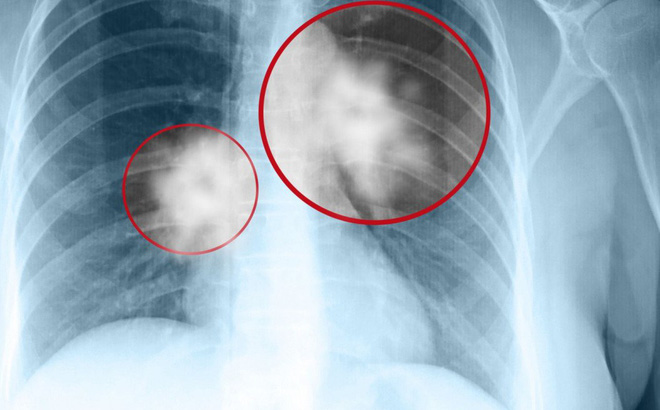

Ví dụ, Chụp X-quang phổi và CT phổi có thể có độ nhạy tương đối khi muốn phát hiện các yếu tố liên quan đến bệnh lao. Bệnh viêm phổi thông qua chụp X quang phổi vẫn có thể nhận thấy kết quả tương đối rõ ràng, nhưng lại đặc biệt khó phát hiện ra dấu hiệu ung thư phổi sớm.

Độ rõ và độ tương phản của kết quả chụp X quang phổi làm giảm khả năng nhìn thấy bệnh đi rất nhiều, vì vậy các bác sĩ chuyên nghiệp sẽ khuyên dùng cách chụp CT phổi nếu bạn là người có nguy cơ mắc ung thư phổi nhiều hơn những người khác.

Hút thuốc lá chính là nguyên nhân chính dẫn đến ung thư phổi. Đối với những người hút thuốc trong thời gian dài, tốt nhất nên kiểm tra CT phổi hàng năm. Nói chung, nếu chỉ khám phổi thông thường hoặc chụp kiểm tra X-quang ngực sẽ rất khó phát hiện ra các dấu hiệu ung thư phổi sớm.